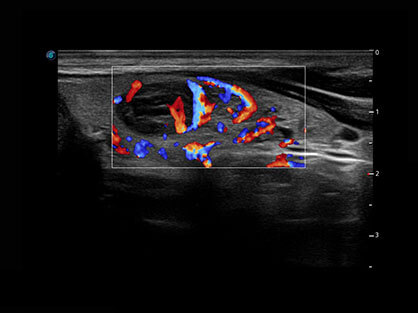

通过对组织运动信息、血流信号及背景噪声进行准确智能的阈值判定,高效提取出微弱血流信号,获得高灵敏度和空间分辨率的血流图像,为临床提供更加真实和丰富的诊断信息。